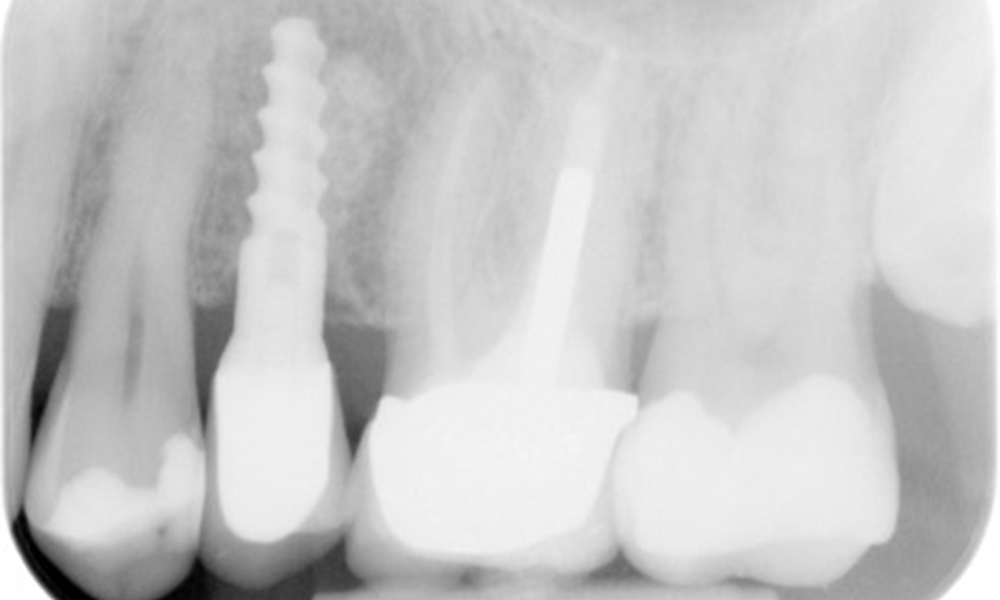

In the medical history, the 55-year-old patient states that he has no systemic disease and is not taking any medication. The patient’s lifestyle is similarly unremarkable. The patient has a few tooth restorations and two implants (2nd and 4th quadrants). On the basis of current findings, gingivitis is identified in an otherwise stable periodontal condition on the reduced periodontium (stage III, grade A).

Previous treatments: dental restorations (non-precious metal/ceramic blend), two implants (2nd, 4th quadrants)

The patient has no particular risk factors with specific dental implications. The key factor, therefore, is the requirement in terms of oral health. In this respect, good oral health is evident with stable, reduced periodontium. Should evidence of an increase in probe depth compared with the baseline, combined with diffuse bleeding, be found at a check-up appointment, diagnosis using X-ray imaging (dental X-ray) should be undertaken in order to identify peri-implant bone loss at an early stage and intervene accordingly.